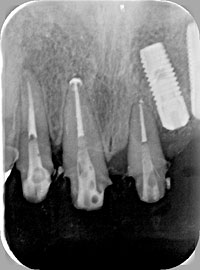

天然歯の歯周組織の骨を回復させ、隣在歯にインプラントを埋入した症例

写真にある変色歯は、歯根破折及び虫歯で歯質が感染崩壊しており、 歯周外科にて確定診断を行い、抜歯しております。

術前 エムドゲイン適応 術後